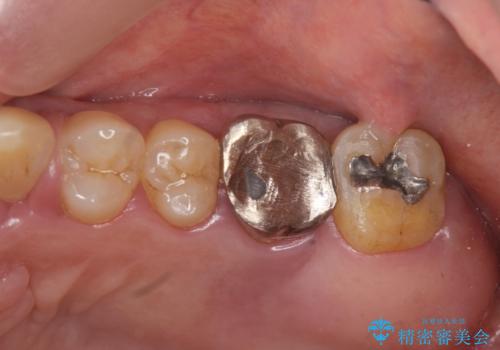

- 夜間のくいしばり、はぎしりが激しく全体的な歯周病が進行し、治療を希望され来院されました。

歯周ポケットの徹底的な除去を行なったのち、歯の揺れを抑え、過大な力がかからぬよう連結クラウン(歯周補綴)を行い強大な力に対抗します。